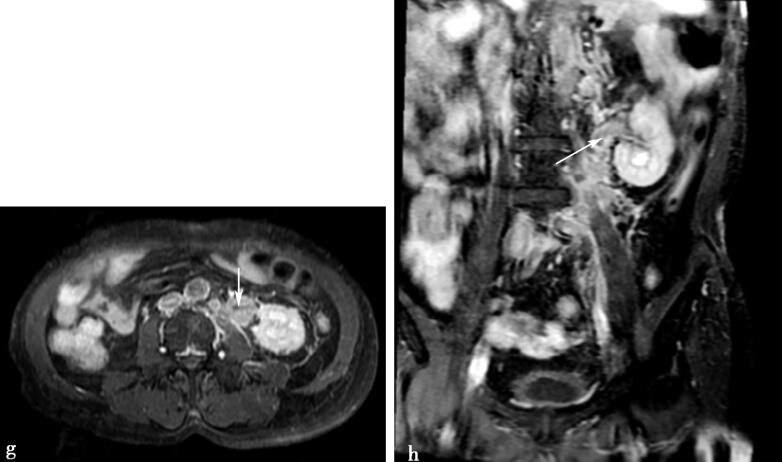

MRI增强扫描

图3g、h,腹部MRI增强扫描,示左输尿管增厚成肿块样,肿块部分中度强化(箭头所示)